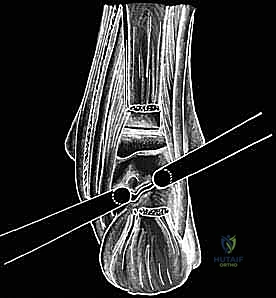

الخطوة الثانية: إحداث الثقوب الجراحية (Portals)

يقوم الدكتور هطيف بعمل شقين صغيرين جداً (بحجم ثقب المفتاح) على جانبي وتر أخيل. هذه الثقوب الدقيقة تضمن عدم المساس بالوتر نفسه.

الخطوة الثالثة: إدخال الكاميرا والأدوات الدقيقة

يتم إدخال كاميرا دقيقة جداً (بقطر 4 ملم) مزودة بتقنية تصوير 4K عالية الوضوح عبر أحد الثقوب. تعرض هذه الكاميرا صورة مكبرة وواضحة جداً للأنسجة الداخلية على شاشة كبيرة، مما يتيح للدكتور هطيف رؤية المفصل بتفاصيل لا يمكن للعين المجردة رؤيتها. يتم إدخال أدوات الجراحة الدقيقة (Micro-instruments) عبر الثقب الآخر.

باستخدام أدوات متخصصة، يقوم الدكتور هطيف بتنظيف الأنسجة الملتهبة، ثم يحدد موقع العظمة المثلثية (Os Trigonum) أو بروز ستيدا المكسور. بمهارة فائقة، يتم تحرير هذه العظمة من الأنسجة المحيطة بها واستئصالها بالكامل وإخراجها من المفصل. يتم أيضاً التأكد من تحرير وتر العضلة المثنية الطويلة للإصبع الكبير (FHL) لضمان حركته بسلاسة دون أي احتكاك.